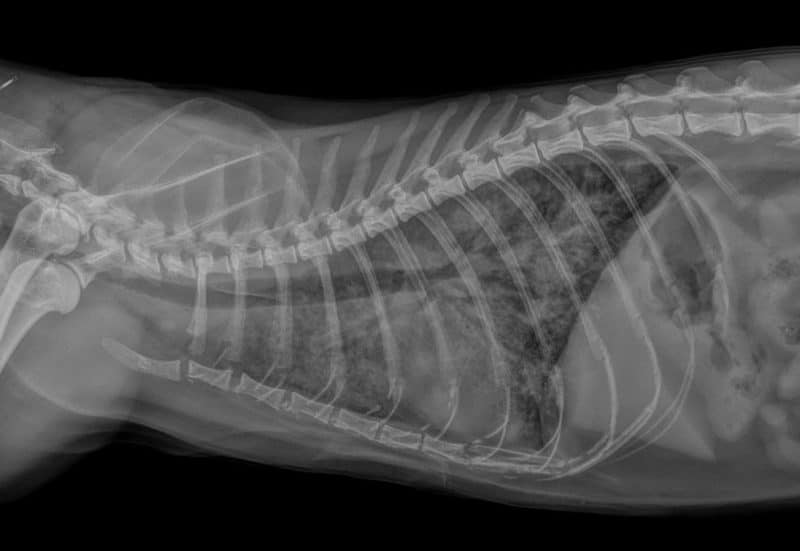

Diagnostic et le traitement des cardiomyopathies chez le chat OnlyVet à Lyon SaintPriest . Programme d'étude de la CMH du Devon Rex (mise à jour 2018) Il s'agit de la maladie cardiaque la plus fréquente chez le chat, avec une prévalence globale de 15 %, un taux allant parfois jusqu'à 29 % chez le chat âgé 1-3.Cette pathologie peut prendre une forme grave et se manifester par une insuffisance.

Source: hsgemsegb.pages.dev Le point sur la cardiomyopathie hypertrophique chez le chat Vets & Clinics , Il s'agit de la maladie cardiaque la plus fréquente chez le chat, avec une prévalence globale de 15 %, un taux allant parfois jusqu'à 29 % chez le chat âgé 1-3.Cette pathologie peut prendre une forme grave et se manifester par une insuffisance. Chez le chat, cette maladie est plus prévalente chez les Ragdolls, les Maine Coon, les chats de.